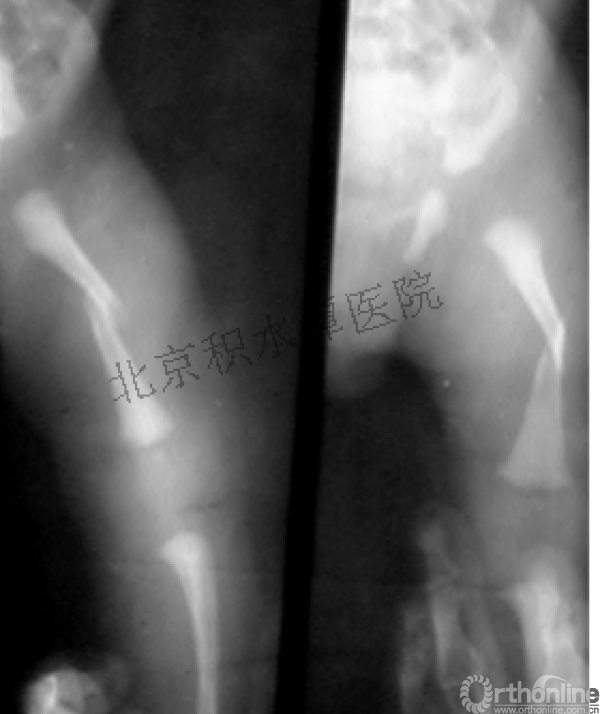

男孩 、5岁,初次骨折于2007年7月。

术后2年→再骨折→再次手术

钢板固定后一年

取板后再骨折→TEN

TEN取出后2个月

闭合复位再固定加尾帽

又过了4年!时间来到2015年